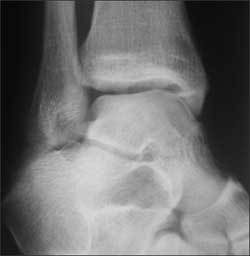

Right ankle pain after a basketball injury: The frontal view of the ankle reveals soft tissue swelling that is predominantly lateral (A, yellow arrow). A small ossific fragment is evident distal to the lateral malleolus (A, white arrow); close inspection shows this to be well-corticated. The remainder of the osseous structures are intact. The lateral view reveals a joint effusion in the talotibial joint (B, arrow); no fractures are visible. In the oblique view (C), the osseous structures appear intact.

The well-corticated ossific fragment is consistent with an old injury, but it is in the region that is now extremely tender. The joint effusion indicates that the current injury is severe. However, this is a nonspecific finding; joint effusions are seen with fractures and ligament and tendon injuries.